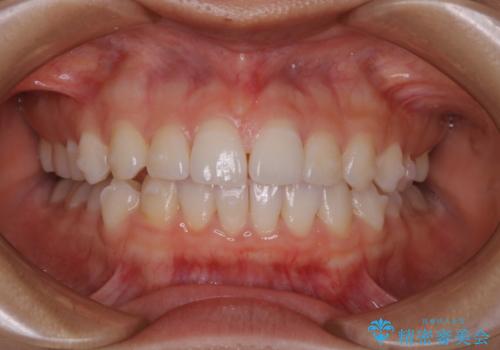

前歯のがたつきをインビザラインで治療

- 上下前歯のがたつきが気になるとの事で来院された患者様です。がたつきの程度が軽度であったため、インビザラインライトにて治療をおこないました。

がたつきの程度が軽度であったことと、インビザラインを正しく装着して頂けたことで短期間で治療終了することが出来ました。